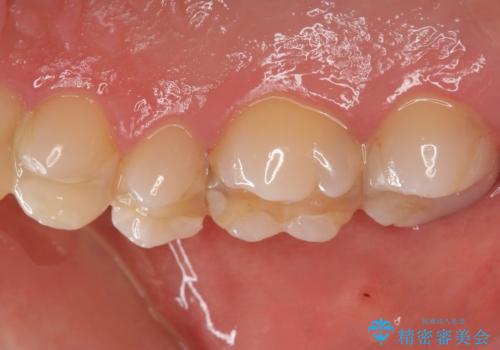

精査したところ、ほとんどの歯が保険内のレジンで充填されており、咬み合わせも悪く咬合していない歯もありました。

虫歯をしっかりと治療したのち、オールセラミッククラウンによる補綴治療を行いました。

不適なレジン充填によるデコボコがなくなったことで歯磨きしやすくなり、また気にされていた咬み合わせも良くなり、ご満足頂けました。